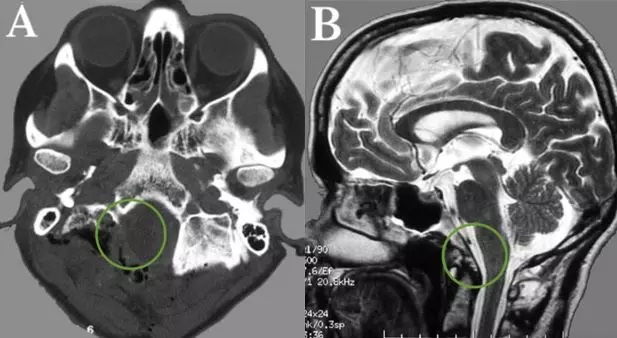

术后CT和MR,显示肿瘤及其被肿瘤侵犯的骨质都切除,肿瘤全切,Simpson一级切除。